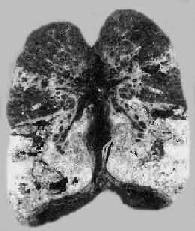

慢性纤维空洞型肺结核病(冠状切面)

图18-8 慢性纤维空洞型肺结核病(冠状切面)

右上叶,左上叶上部和左下叶上部都有厚壁空洞形成;肺门淋巴结无结核病变